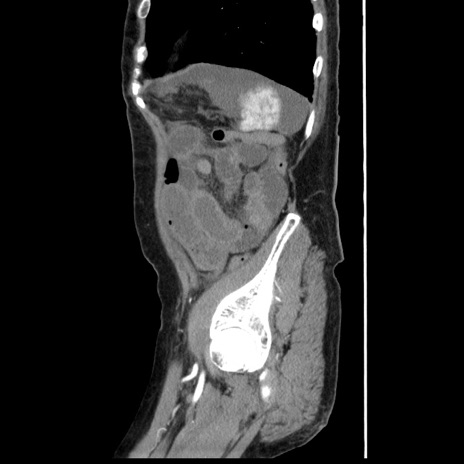

冠状断像

【症例】80歳代女性

【主訴】腹痛

【現病歴】8時間前から腹痛あり来院。

【既往歴】糖尿病、脂質異常症、子宮体癌にて子宮全摘術

【身体所見】意識清明・会話良好だが腹痛で苦悶様、全腹部にわたって反跳痛と圧痛あり

【データ】WBC 13600、CRP 0.14、LDH 224、CK 90